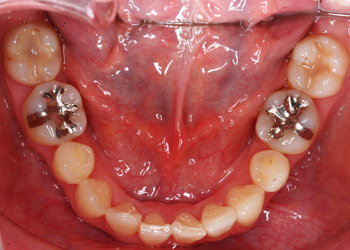

叢生(そうせい)